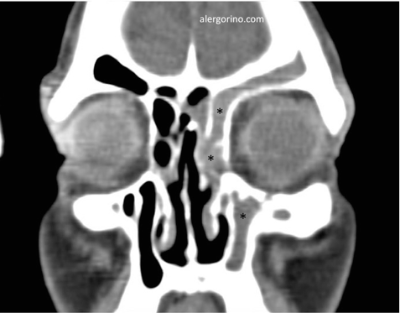

El diagnóstico se realiza mediante la historia clínica y una endoscopia nasal que proporcionan datos como la presencia de pólipos, la descarga mucopurulenta y el edema o la obstrucción de las áreas de drenaje de los senos paranasales. Si no se produjera una respuesta al tratamiento médico se evalua la situación de los senos paranasales mediante una tomografía computarizada (TC).